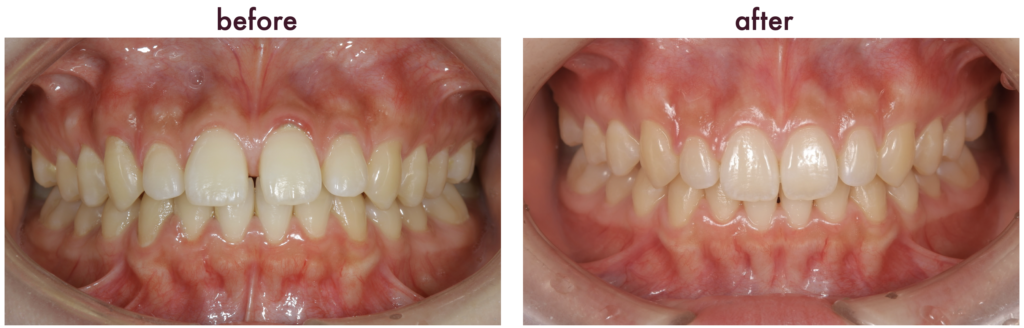

こちらの写真はインビザラインにて矯正治療を行った例になります。見た目ももちろんですが、噛み合わせも改善し、非常に綺麗な歯ならびになりました。

インビザラインは、特に見た目を気にされる方や、固定装置が不便な方に選ばれることがありますが、治療の適応や効果には個人差があります。適応症も様々ございますので、自身の状態に合った矯正方法を選ぶことが重要です。当院では無料矯正相談も行っております。矯正治療について気になること等ございましたらご連絡いただけたらと思います。